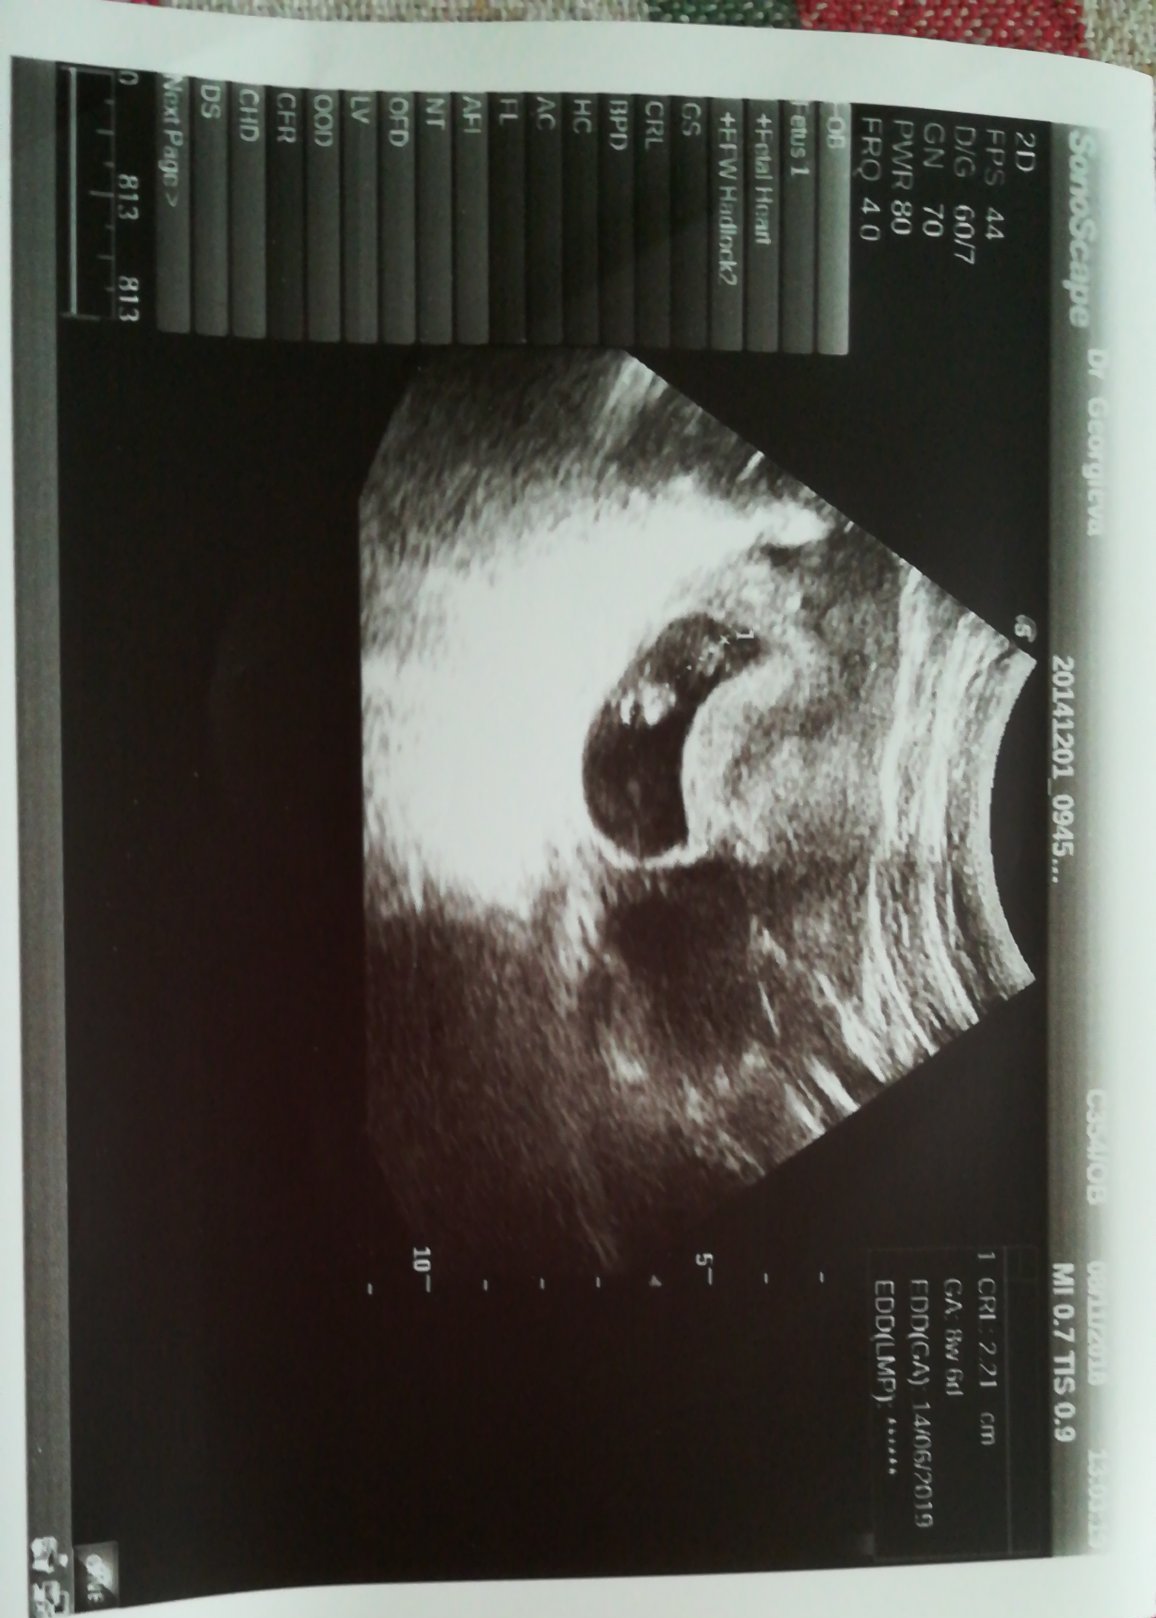

Какви са обичайните състояния на ендометриума и жълтъчното мехурче в ранните седмици на бременността?